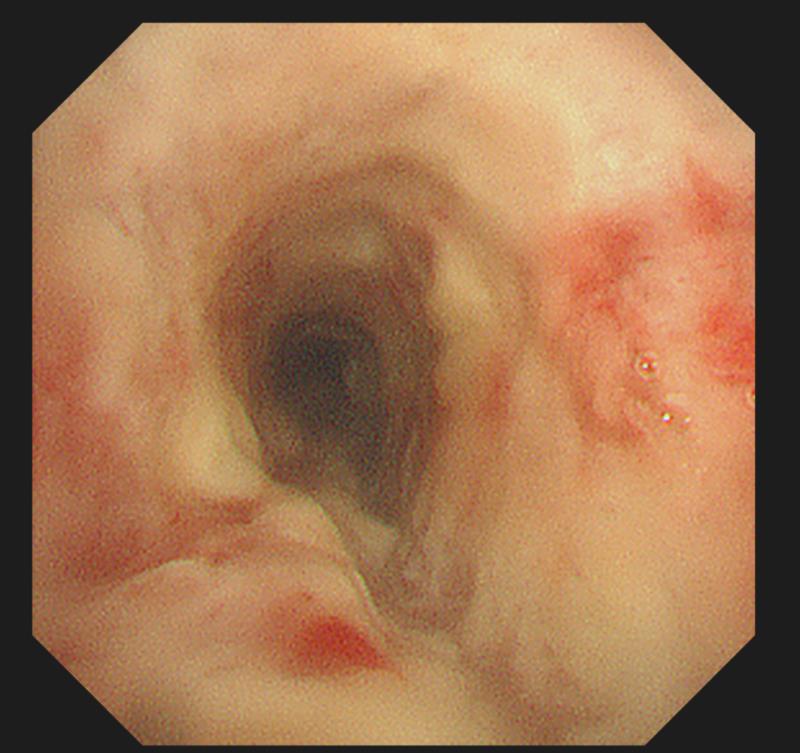

在武汉市肺科医院内镜中心,医生通过呼吸内镜进入小梁的气管、支气管进行检查发现,从咽喉到气管、左右支气管,密密麻麻长满了干酪样的结核病灶。所幸,经过积极的药物和气管镜介入治疗,小梁的病情迅速得到了控制。